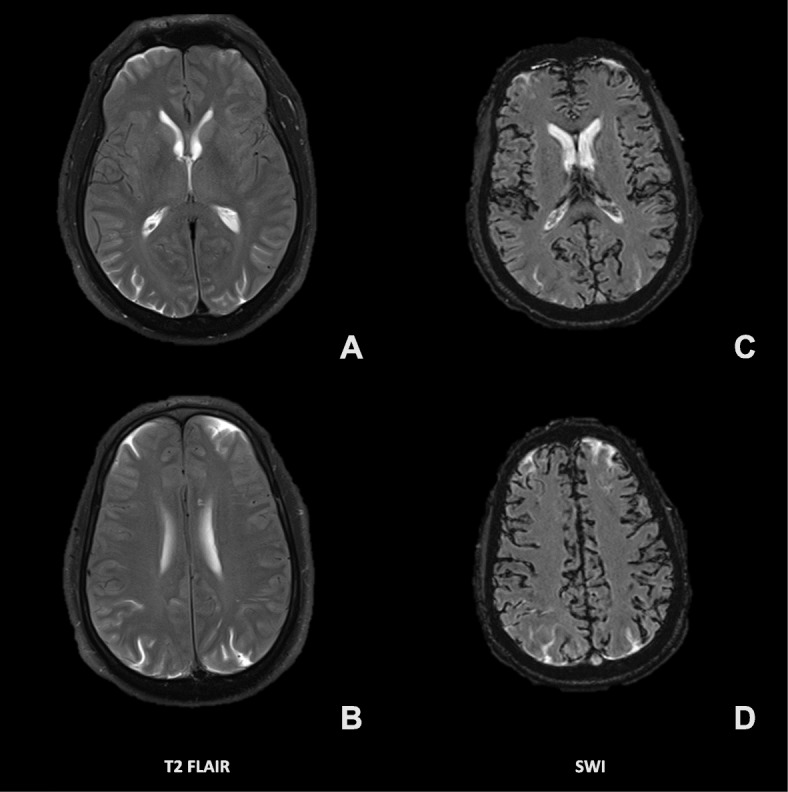

Computed tomography (CT) of the head without contrast (Fig. 2) was obtained just under 12 h after blood injection. This imaging was remarkable for diffuse cortical sulci obscuration, with preserved grey white matter differentiation. Non-contrast 1.5 T magnetic resonance imaging (MRI) of the brain (Fig. 3) was obtained about 14 h after blood injection. On T2 fluid-attenuated inversion recovery (FLAIR), there was diffuse sulcal and ventricular hyperintensity consistent with diffuse spread of blood products or inadequately subtracted CSF. On susceptibility weighted imaging (SWI), there was diffuse susceptibility artifacts. This imaging was consistent with diffuse infiltration of blood products throughout the CSF. Additionally, MRI of the lumbar spine showed T1 hypointensity and T2 hyperintensity in the epidural and subarachnoid space, with T2 blooming artifact in the thecal sac. Lumbar spine imaging was consistent with blood products in both the epidural and subarachnoid spaces, possibly from mixed intrathecal and epidural blood injection, without hematoma.

Fig. 3.

Non-contrast 1.5 T magnetic resonance imaging (MRI), taken 14 h after intrathecal blood injection, with both fluid-attenuated inversion recovery (FLAIR; a, b) and susceptibility weighted imaging (SWI; c, d)